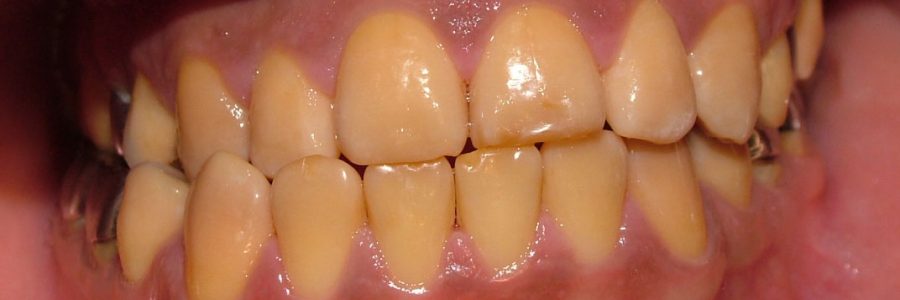

Paciente con progenie, asimetria esqueletal y piezas dentarias con falta de la capa de esmalte.Tratamiento: Ortodoncia, Cirugía y Rehabilitación. (V. Barra)